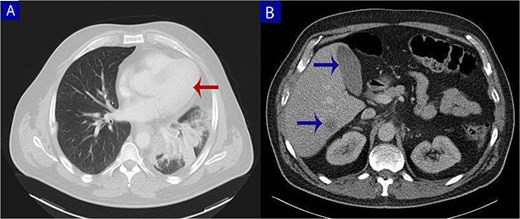

A 49-year-old male with a 20-pack-year smoking history and occasional alcohol consumption presented with a painful, nodular skin lesion on his upper back. The lesion had been present for ~1 month and had progressively increased in size. Clinically, it appeared as a solitary, firm, erythematous nodule with central ulceration and overlying necrotic crust, measuring ~1.5 × 1 cm and surrounded by a violaceous inflammatory halo (Fig. 1). A partial excisional biopsy was obtained from the center of the lesion. Histopathological examination using hematoxylin and eosin staining revealed a poorly circumscribed, infiltrating tumor within the dermis. The tumor is composed of cords and nodules of atypical cells dissecting between collagen bundles, with focal areas of gland formation. The tumor extends into the subcutaneous adipose tissue and surrounding soft tissue in an irregular infiltrative pattern. The findings confirmed invasive adenocarcinoma (Fig. 2), prompting further evaluation to assess for metastatic spread. Contrast-enhanced computed tomography (CT) of the chest, abdomen, and pelvis demonstrated a lobulated mass with heterogeneous enhancement centered at the left pulmonary hilum, invading adjacent bronchi and vascular structures (Fig. 3A). Multiple hypodense lesions in the liver were consistent with hepatic metastases (Fig. 3B). Additionally, numerous lytic bone lesions were noted involving the ribs, vertebral bodies, sternum, and right pubic bone, indicating widespread skeletal metastases.A positron emission tomography–computed tomography (PET-CT) scan was not performed due to lack of availability in Syria. Bronchoscopy revealed complete obstruction of the left upper lobe bronchus, and a biopsy was obtained from the lesion. Histopathological examination demonstrated features consistent with invasive high-grade HAC, characterized by large polygonal cells with abundant eosinophilic cytoplasm and prominent nucleoli, resembling HCC morphology (Fig. 4). To further support the diagnosis, immunohistochemical staining was performed. The tumour cells showed strong positivity for CK7, HepPar-1, and CK19 (Fig. 5), and were negative for TTF-1, Napsin-A, p40, alpha-fetoprotein (AFP), and Glypican-3. Serum AFP level was within normal limits. This immunoprofile supports the diagnosis of HAC of pulmonary origin. In addition, immunohistochemical staining for HepPar-1 was performed on the biopsy from the subcutaneous metastasis, which also showed positive staining (Fig. 6). This finding further supports the lung as the primary site of the hepatoid carcinoma, given the matching immunophenotype between the primary lung tumour and the cutaneous metastasis.

Contrast-enhanced computed tomography (CT) of the chest, abdomen, and pelvis. (A) Axial chest CT shows a lobulated mass (arrow) with heterogeneous enhancement centered at the left pulmonary hilum, invading adjacent bronchial and vascular structures. (B) Abdominal CT reveals multiple hypodense lesions in the liver (arrows), consistent with hepatic metastases.